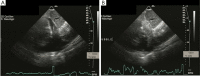

Echocardiographic guidance has an important role in percutaneous cardiovascular procedures and vascular access. The advantages include real time imaging, portability, and availability, which make it an effective imaging modality. This article will review the role of echocardiographic guidance for diagnostic and therapeutic percutaneous procedures, specifically, transvenous and transarterial access, pericardiocentesis, endomyocardial biopsy, transcatheter pulmonary valve replacement, pulmonary valve repair, transcatheter aortic valve implantation, and percutaneous mitral valve repair. We will address the ways in which echocardiographic guidance provides these procedures with detailed information on anatomy, adjacent structures, and intraprocedural instrument position, thus resulting in improvement in procedural efficacy, safety and patient outcomes.